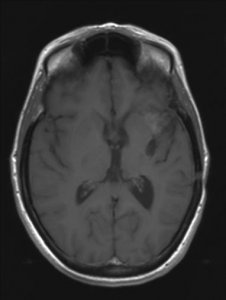

Een astrocytoom graad III groeit onbehandeld snel door in het omliggende hersenweefsel; de ziektegeschiedenis is daarom meestal relatief kort. De meeste patiënten zijn tussen de 30 en 50 jaar oud, iets vaker mannen dan vrouwen. Een MRI toont meestal een grillige, slecht begrensde tumor die met contrast kan aankleuren. De diagnose moet gesteld worden door onderzoek van het weefsel.

'Hoe is het mogelijk, dit kan niet, dit is bizar, zoiets heb ik nog nooit gezien maar het is waar'. Dit waren de woorden van de neuro-oncoloog. Mijn vriendin Ineke en ik bogen ons naar haar computer waar het onverklaarbare resultaat stond. Op de MRI-scan was te zien dat de kwaadaardige tumor zich had teruggetrokken. De tumor had een donkere holte met een grillige tumorrand achtergelaten. De neuro-oncoloog benadrukte nog eens dat het echt heel bijzonder was en dat zij en de radioloog voor een raadsel stonden. Ik vroeg haar wat dit betekende voor de prognose van mijn levensverwachting. Ze zei dat er nog één of misschien zelfs twee jaar zou bijkomen. Meer durfde ze er ook niet over te zeggen.

De MRI scans van 2006 en 2007 zijn niet correct geïnterpreteerd. Wat toen als tumorgroei werd gezien blijkt nu een reactie van de bestraling te zijn. De chemokuur was overbodig omdat de tumor niet groeide. Wat je nu ziet is de tumor die enigzins gegroeid lijkt, maar dat is niet zeker. Als het zeker is moet je overwegen om opnieuw bestraald te worden. Meer patienten zijn ook met de verkeerde boodschap (dat de tumor groeit) naar huis gegaan,ook in andere ziekenhuizen.

Je moet je realiseren dat een MRI een plaatje is waarop een proces zichtbaar wordt oa door aankleuring met contrast. Met een MRI kun je dus vervolgen of een “proces” groter of kleiner wordt. Maar een MRI geeft geen inzicht in de aard van het proces, je weet niet welke cellen toegenomen zijn.

De MRI na de bestraling liet zien dat het ‘proces”in jouw hersenen gegroeid was. Omdat men wist met een kwaadaardige tumor te maken te hebben, is daaruit de op dat moment voor de hand liggende conclusie getrokken dat de radiotherapie helaas niet geholpen had. Na de aanname dat de radiotherapie niet geholpen leek te hebben heeft men het voorstel voor chemotherapie gedaan. Naar mijn mening op goede gronden. Helaas blijkt vaker dat als de tijd verstrijkt je voor verrassingen kan komen te staan zoals ook in jouw geval. Toen na een hele tijd een MRI werd herhaald bleek ‘het proces’in de hersenen eerder kleiner te zijn geworden dan de groei die men eigenlijk had verwacht. Op dat moment heeft men de conclusie moeten trekken dat de toename van het proces na de bestraling dus een gevolg moet zijn geweest van de bestraling een soort oedeem (zwelling) tgv de straling. Deze conclusie is echter alleen te maken door het beloop in de tijd en deze conclusie was niet te maken in een eerder stadium.

Dit betekent ook dat het vanaf nu wel zinnig is om met enige regelmaat de MRI te vervolgen. Mocht er ooit weer op de MRI een toename van het proces gezien worden dan is namelijk opnieuw radiotherapie een goede behandelingsmogelijkheid. (chemo ligt wat minder voor de hand omdat je dat slecht hebt verdragen).Je moet alleen pas overwegen te gaan behandelen als op de laatste MRI duidelijk een groei te zien is van het proces, weet jij of de laatste MRI een verschil aangaf met de vorige? Als je het goed vindt kan ik in het UMCG ook de gemaakte MRI’s van jou bekijken als het jou niet helemaal duidelijk is geworden.

Op de scan was sprake van enige aankleuring, maar de neuro-oncoloog is er van overtuigd dat het geen tumorgroei is maar nog een oedeem van de bestraling. Volgens haar duwt de tumor andere cellen aan de kant en een oedeem doet dat niet. Bovendien is de aankleuring ook a-typisch wat betekent dat hij niet als ronding begint en juist dát hoort bij een glioom.